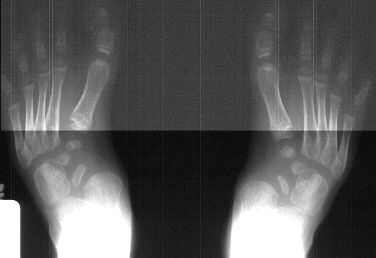

A 6 year old white male presents with a history of an undiagnosed

skeletal dysplasia. Previous surgery includes bilateral femoral

and tibial osteotomies for valgus deformities. His knee alignment

is now normal. His main complaint is the development of painful

callus over the arch of his foot and difficult in fitting shoes.

These deformities of the feet have been getting worse by the description

given by the mother. His foot deformity has never been treated

with casts or splints. On examination he has a short thick foot

with a kidney bean shaped curve to its lateral border. The arch

is not high but has a heavy callus bilaterally. The following

bilateral foot deformities were also present on physical examination:

hindfoot valgus of approx. 20-30 degrees, metatarsus adductus,

and prominence of the talar head in the medial arch with thickened

callus over the bony prominence.